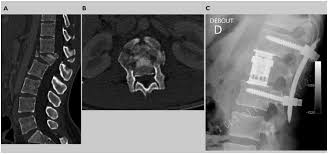

Prise En Charge Des Fractures A Haute Et Basse Energie Traumatique De La Colonne Thoracique Et Lombaire Revue Medicale Suisse

Prise En Charge Des Fractures A Haute Et Basse Energie Traumatique De La Colonne Thoracique Et Lombaire Revue Medicale Suisse from www.revmed.ch